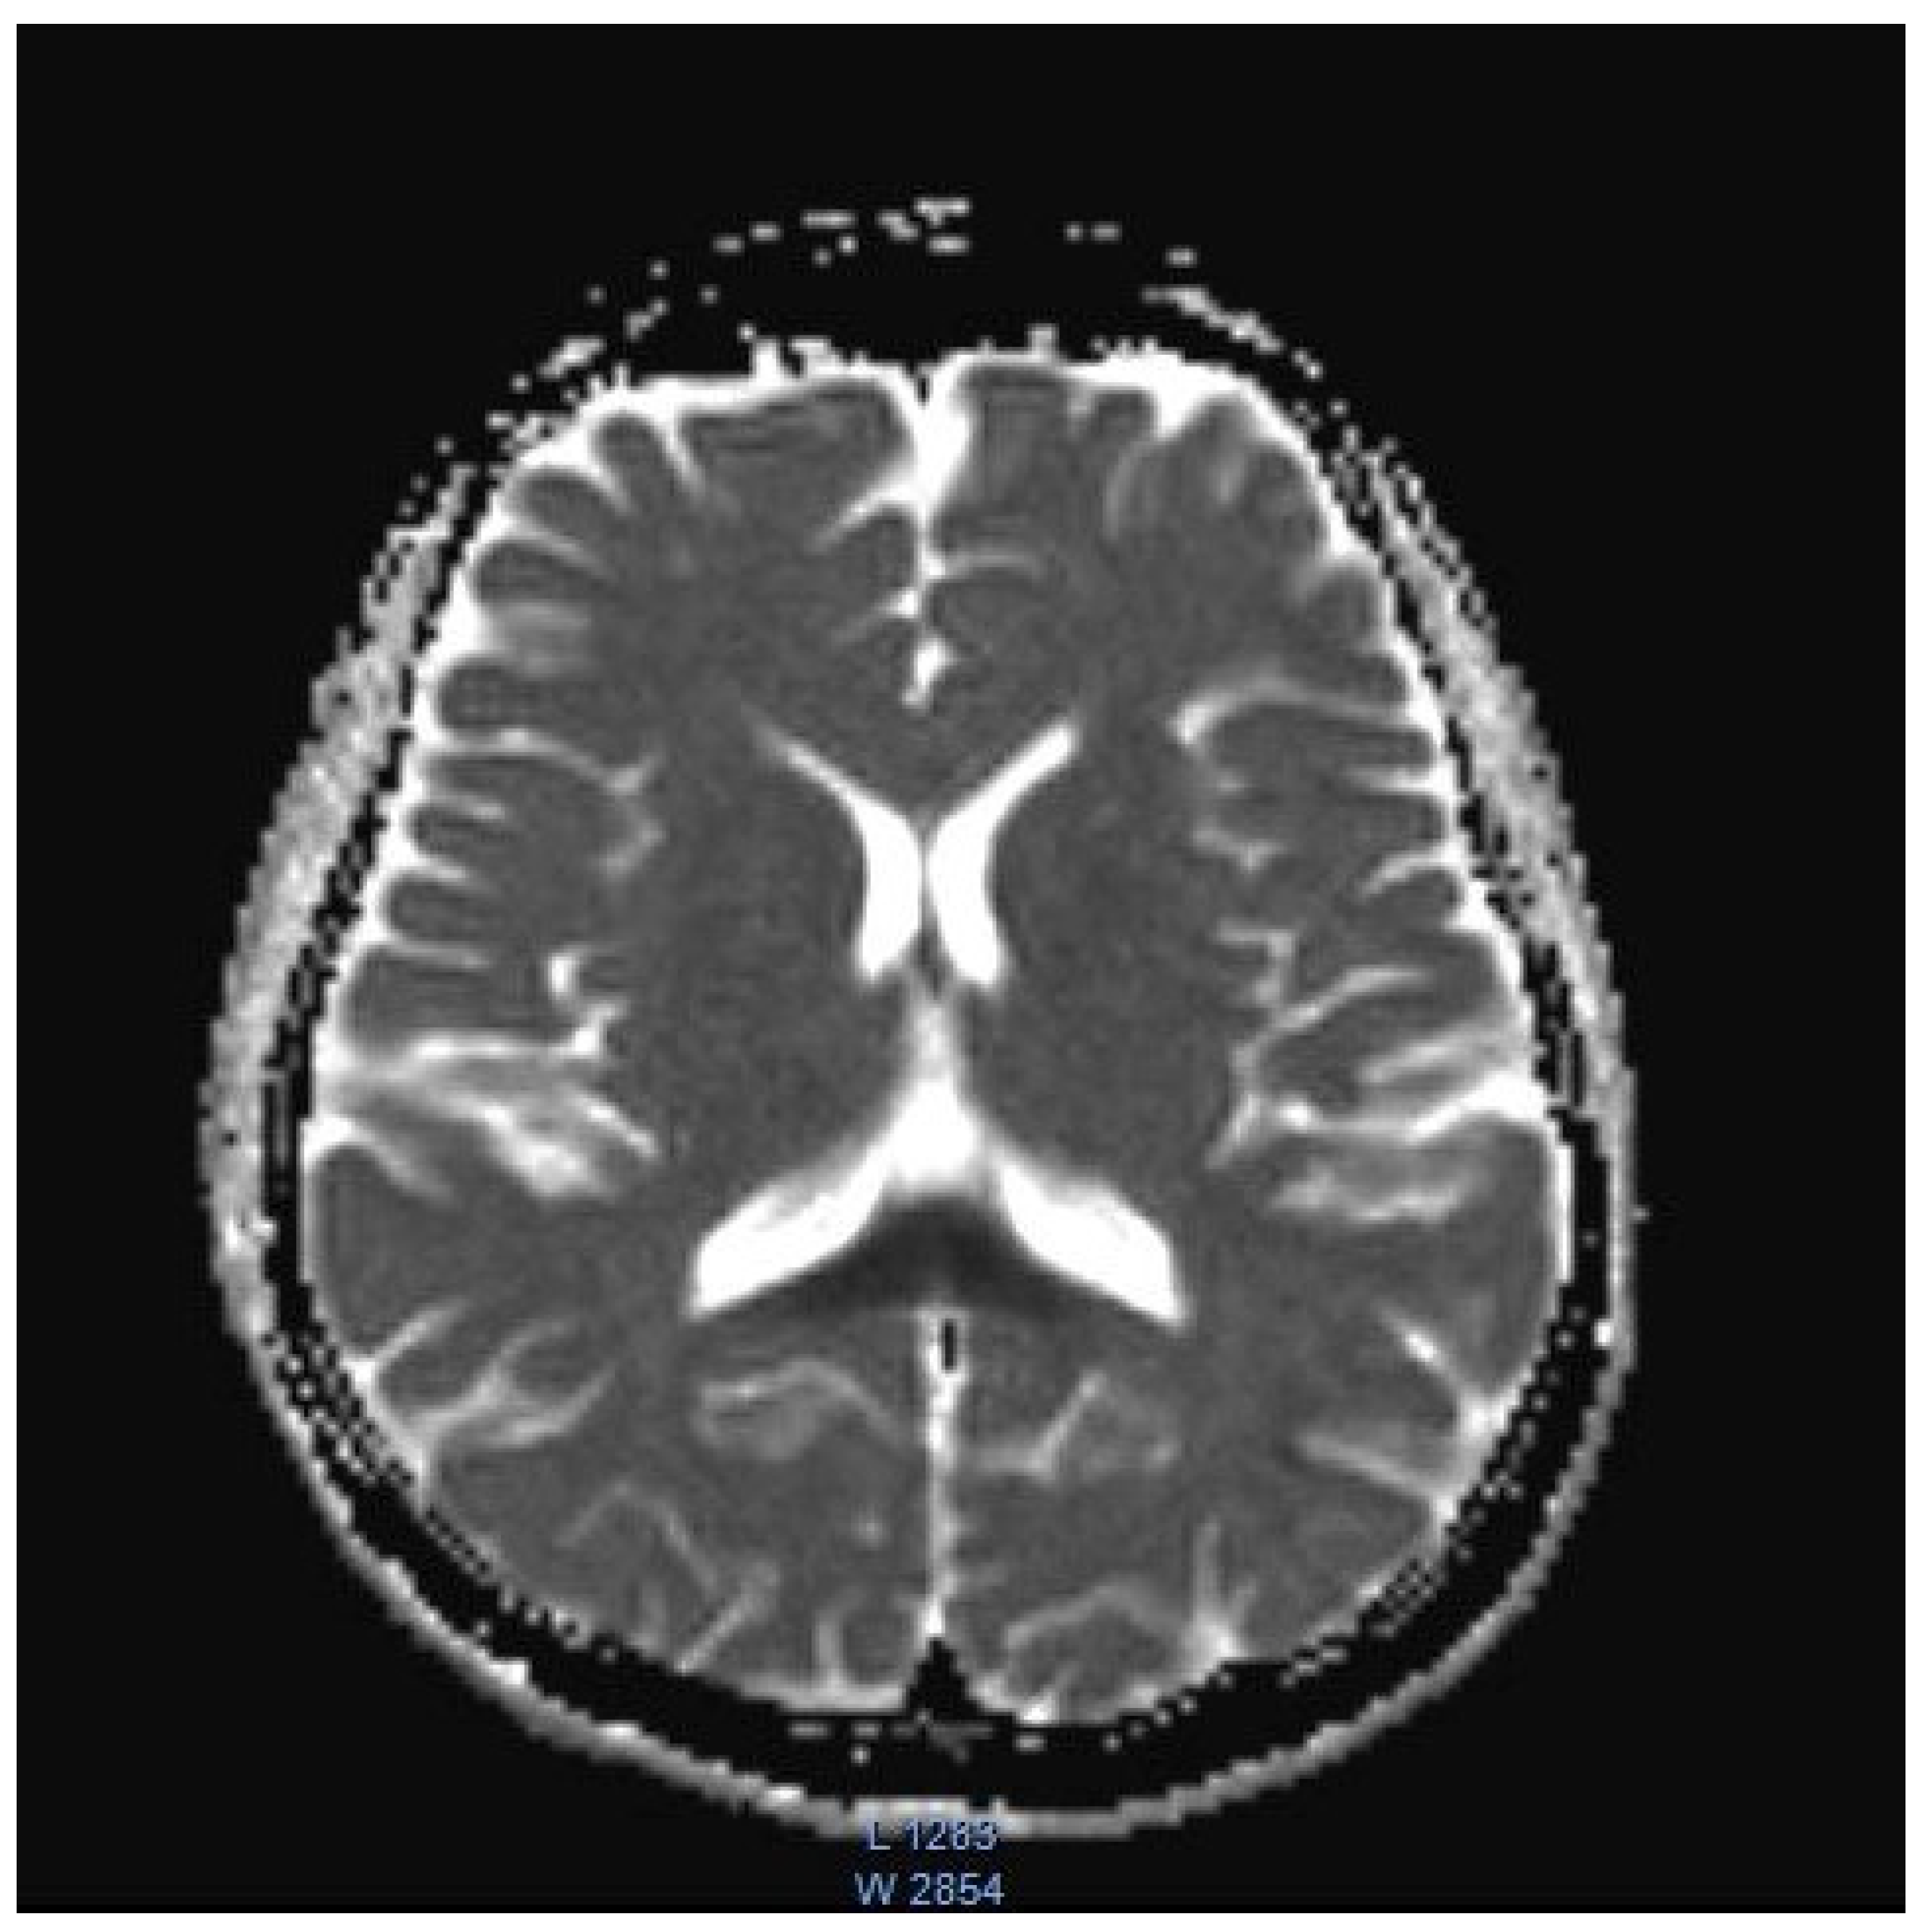

| Cecil, 2002, USA [3] | 17, M | Crohn’s disease | N/A | N/A; N/A | Gait instability; Polyneuropathy; visual disturbance; tremor | T2: Symmetrical hyperintensity in the substantia nigra, red nucleus, globus pallidus, the putamen, caudate body, caudate heads and medial thalami | Near complete resolution | Near complete resolution |

| Chang, 2021, USA [4] | 14, M | Clostridium difficile enterocolitis | N/A | N/A; N/A | Altered mental status; stiffening of 4 extremities; visual disturbance; slurred speech; gait instability | T2: symmetrical hyperintensity with corresponding diffusion restriction on DWI in posterior frontal, parietal, and occipital periventricular white matter and splenium of the corpus callosum | Near complete resolution | Near complete resolution |

| Omrani, Iran, 2020 [8] | 11, M | Febrile bloody diarrhea | 12 g | N/A; N/A | Tinnitus; hearing loss; aggressive behavior; generalized dystonia; generalized tonic-clonic seizure; decreased level of consciousness. | T2: Symmetrical hyperintensity in dentate nuclei, substantia nigra, globus pallidi, splenium of the corpus callosum, and centrum semiovale | Improvement | Partial improvement |

| Patel, USA, 2020 [9] | 8, M | Prophylaxis after small bowel transplantation | 1378.8 g | Three years; three years | Ataxia | T2: Symmetrical hyperintensity in the dentate nuclei, inferior olivary nuclei, putamen, and corpus callosum | Resolution | Resolution |

| Sudan, 2016, India [11] | 14, M | Acute abdominal pain | N/A | 3; 5 | Dysarthria; altered mental status; seizures. | T2: symmetrical hyperintensity in the optic tracts, dorsal midbrain, inferior olivary nuclei, peri-aqueductal white matter, superior and inferior colliculi, superior cerebellar peduncle, dentate nuclei, medulla oblongata, and cervical spinal cord segment extending from the cervicomedullary junction to C6-C7 level DWI: restricted diffusion in the splenium of the corpus callosum | N/A | Resolution |